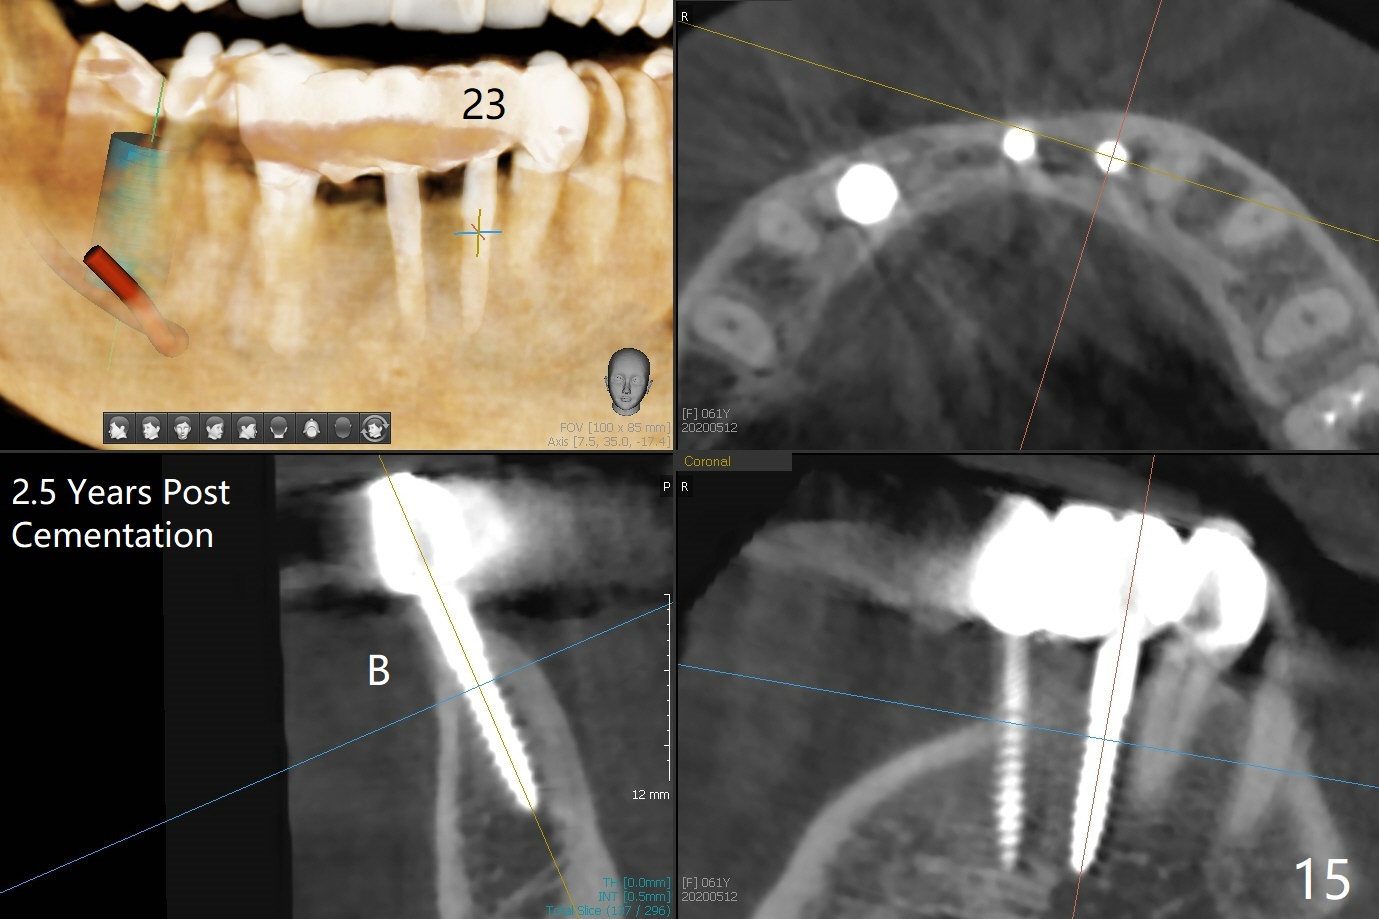

The mesial defect at #27 appears to have been repaired 8 months postop (Fig.8,9 *); there is no bone loss at 1-piece implant sites. The gingival recession seems to remain the same before and after removal of the provisional FPD (Fig.10,11). The bulging abutment at the cervix is less prominent when a straight abutment is used and prepared (Fig.12, 4.5x5.5(5) mm). There is no bone loss at #23, 25 and 27 sites 2.5 years post cementation (Fig.12-15), although the trajectory of the implants could be improved by using surgical guide (Fig.16-18).